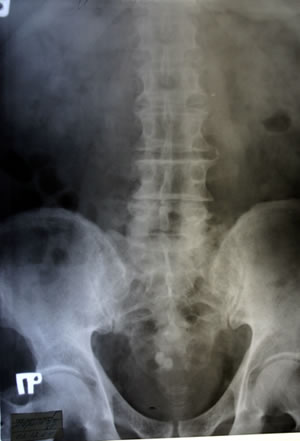

ОБЗОРНАЯ

УРОГРАФИЯ: |

| |